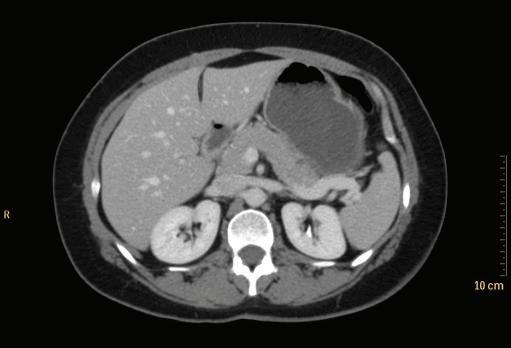

FIGURE 1-17 Axial CT of the abdomen.